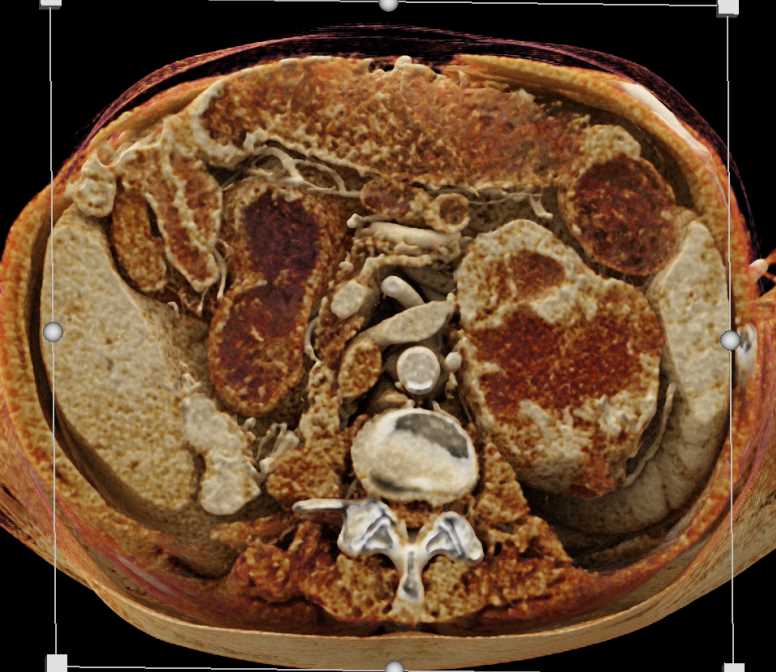

Pheochromocytoma Right Adrenal Gland